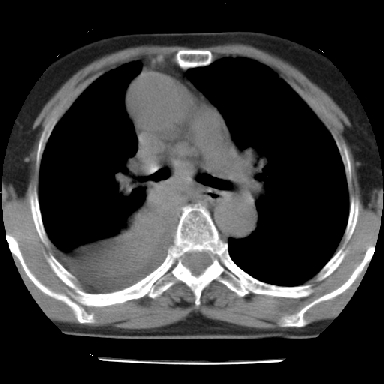

以下是引用苯小孩在2007-4-13 16:20:00的发言:[br]1、右下肺中央型肺癌并阻塞性肺不张、肺内转移、胸椎右侧附件亦有转移<横断层面第8层>.[br]2、右侧胸腔积液.

以下是引用swyyy2007在2007-4-13 15:31:00的发言:[br]右肺门下区肿块,右肺下叶支气管阻塞,右肺下叶不张,右侧大量胸腔积液,右肺中叶见结节状高密度影,边缘清,纵隔内见肿大淋巴结。首先考虑右下肺中心型肺癌伴右肺下叶不张、中叶、纵隔淋巴结转移。右侧胸腔积液。